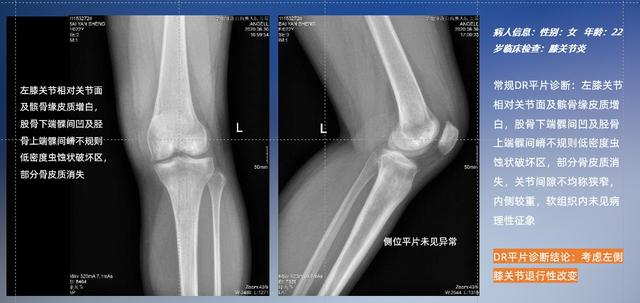

以膝关节疾病检查为例,膝关节在解剖学意义上是一种较为复杂的最大关节,由胫骨上端、股骨下端及髌骨组成。在股骨与胫骨的关节面之间存在两块半月板,分别处于内侧、外侧。膝关节的运动主要为伸、屈,在半屈位时可进行小幅度的旋外、旋内运动。随着现代人们体育生活以及肥胖的增加,膝关节疾病出现高发趋势,特别是关节磨损、膝关节炎与骨关节炎等关节退行性改变,长时间的内翻负荷会造成内侧关节软骨、骨性关节面的磨损。目前针对此类疾病的检查主要为平片下的负重位检查、CT检查以及MRI检查,相较于非负重位检查,负重位检查能更加真实反映膝关节结构中胫骨、股骨、髌骨实际对位关系和关节面的形态特征及关节间隙大小,对膝关节骨关节病诊断准确率高。

普通平片扫描与WR-3D扫描前后诊断结果对比

在负重位状态下,数字化X线三维扫描与重建,能够更好的呈现受检者关节受力改变的状态。亿万28入口网页版-亿万28网页在线玩-万28官网下载最新版-亿万e网址pg-亿万28pg电子-亿万28赏金女王-亿万28娱乐科技创新的WR-3D动态三维影像重建系统,通过数字化X线摄影完成三维扫描并重建三维影像信息,包括断层图像重建、MPR多平面重建、MIP重建以及VR体绘制。其扫描时间短,剂量相较于CT设备大幅缩减,同时成本更低,在临床诊断以及医疗方案制定中具有极大的价值意义。而相较于普通平片下的负重位扫描,负重位动态三维影像重建技术能够避免二维状态下的组织结构重叠、密度分辨率不足、组织解剖结构难以分辨等问题。WR-3D支持多角度的三维观察,能全面的呈现被检查部位在多个角度下的三维影像信息,极大的降低了二维负重位检查带来的漏诊率。